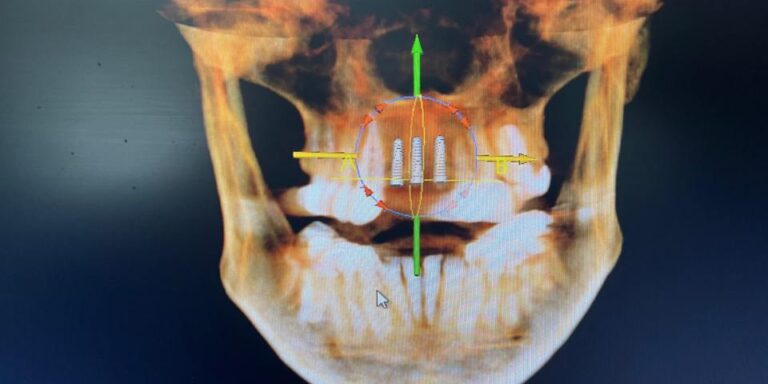

Explore a full range of advanced oral surgery procedures designed to restore health, function, and confidence. Our board-certified Oral and Maxillofacial Surgeons provide expert care in dental implants, wisdom teeth removal, tooth extractions, bone grafting, and sedation anesthesia. Using state-of-the-art technology and a patient-first approach, every procedure is performed with precision and comfort in mind. Whether you need a single treatment or comprehensive surgical care, our team is committed to delivering safe, effective solutions tailored to your needs and long-term oral health goals.